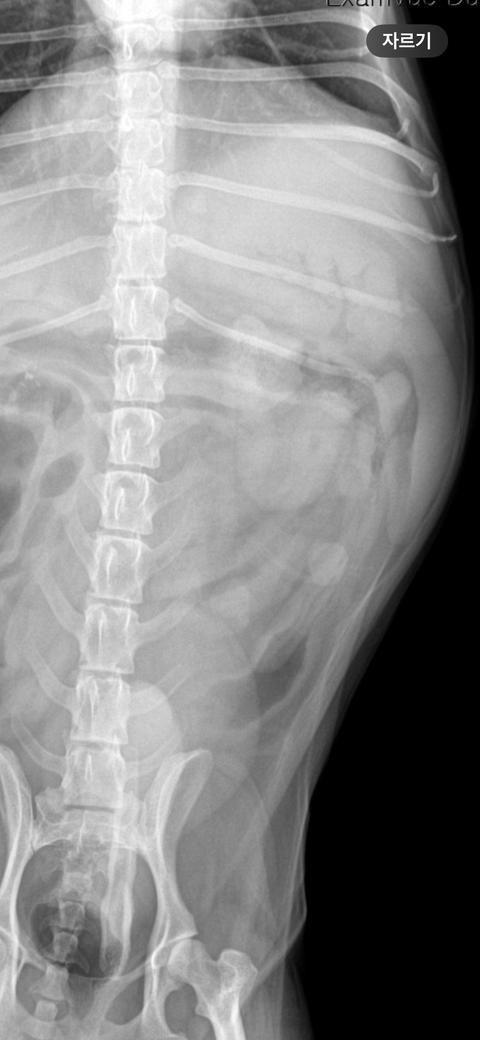

엄마가 2일 전과 1일 전에 시츄에게 족발을 주어서 2일 전부터 간헐적으로 토하다가 금일 새벽에 12번 정도 토를 하고 2cm 정도 되는 뼈를 토했습니다. 그리고 변도 조금씩 묽게 싸고 금일 새벽에 뼈를 포함한 저런 똥을 쌌습니다. 사진에 보시다시피 피가 살짝 섞여있습니다. 그래서 병원을 방문하였더니 위에 뼈가 있는 것이 아니라 소장에 가로 2.7cm 세로 2cm 정도의 뼈가 들어있는 거 같다고 판단하셨습니다. 강아지가 11살이라 나이도 있고 디스크로 인해 스테로이드를 3주 정도 복용하여 간수치가 좋지 않다고 하여 수술을 해야 할지 고민이 된다고 하시고 당장 수술을 결정하자니 뼈가 그리 크지 않아 위에 사진처럼 나올 수도 있을 거 같다 보호자 의견에 따르겠다고 말씀하셨습니다. 수술을 결정하지 않는 판단을 보호자가 하신다면 오늘 5시간 정도 수액을 맞고 엑스레이를 다시 찍어본 후 뼈가 좀 내려갔는지 확인을 해보면서 지켜보는 방향으로 가자고 하셨습니다. 하지만 금일은 금식 금수이지만 내일 밥을 주고 물을 줬을 때 토하게 된다면 병원에 방문하여 수술을 고려하자고 하셨습니다. 수의사 선생님들의 의견을 듣고 싶습니다..

주치의의 판단이 옳은 부분이 많지만, 통상 구토를 12번이나 할정도로 이물 폐색 가능성이 높으면서 방사선 사진에서 폐색부가 저런 양상으로 보인다면 바로 배를 여는게 교과서적인 추천사항입니다.

폐색이 유지되면 이차적인 췌장염과 장괴사가 가능하여 환자를 잃을 수 있으니 방사선 사진을 다시 촬영하시고 이물이 관찰된다면 바로 배를 여는것을 추천합니다.